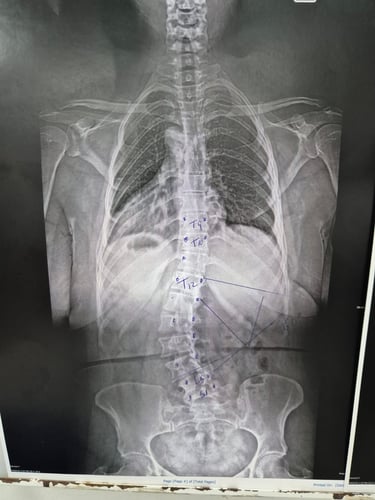

Escoliosis y problemas de columna

Gallery

Provide a short description of the gallery, highlighting key things.